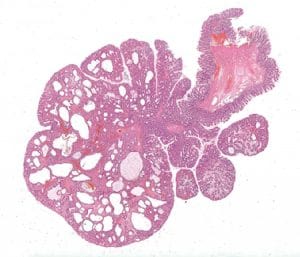

From the chapter “Genetic tumour syndromes of the digestive system,” juvenile polyposis syndrome.